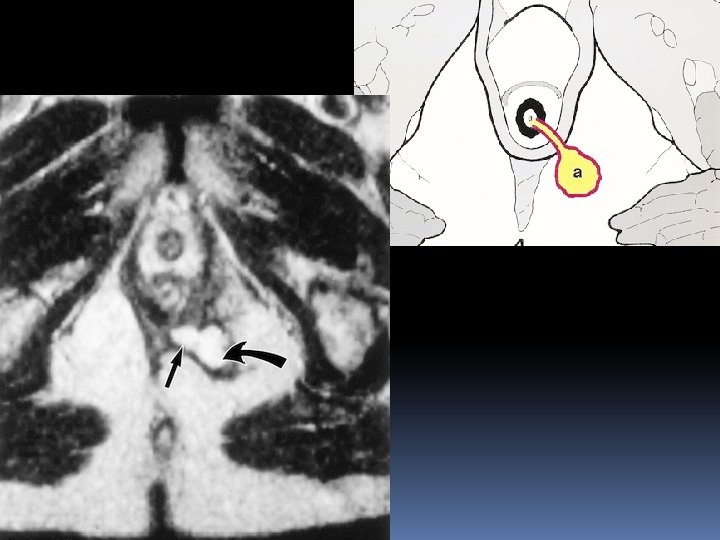

Extrasphincteric fistula A small abscess in left ischeoanal fossa , the fistula runs through levator ani , it is therefore above the sphincter complex and extrasphincteric